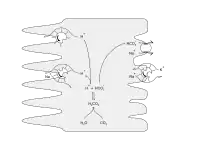

Renal corpuscle Diagram outlining movement of ions in nephron.

Diagram outlining movement of ions in nephron.